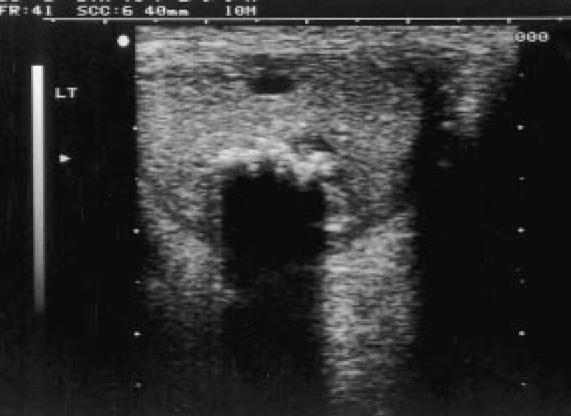

A 63-year-old man presented with a painless lump in his left testis that had first been noticed 4 months previously. A large mass (3 cm in size) was palpable in the lower pole of the left testis.There was no lymphadenopathy, palpable intraabdominal masses, nor gynaecomastia. Ultrasonography of the lesion emonstrated a hypoechoic solid mass posteriorly in the lower pole of the left testis containing multiple calcific foci associated with dense distal acoustic shadowing (Fig. 1).

Fig. 1. The appearance of the calcified epidermoid cyst on ultrasonography. A hypoechoic solid lesion is identified within the lefttestis (longitudinal section) that contains prominent calcified foci with ssociated distal acoustic shadowing.

No significant colour flow was identified within the lesion on colour Doppler ultrasound examination. Orchidectomy was performed and histology demonstrated a benign epidermoid cyst containing keratinising squamous epithelium and keratin debris with dystrophic calcification. There was no evidence of testicular intraepithelial neoplasia in the adjoining tissue.